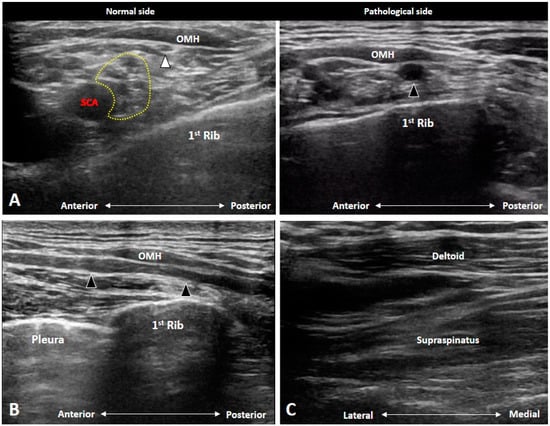

4.5. Thoracic Outlet Syndrome